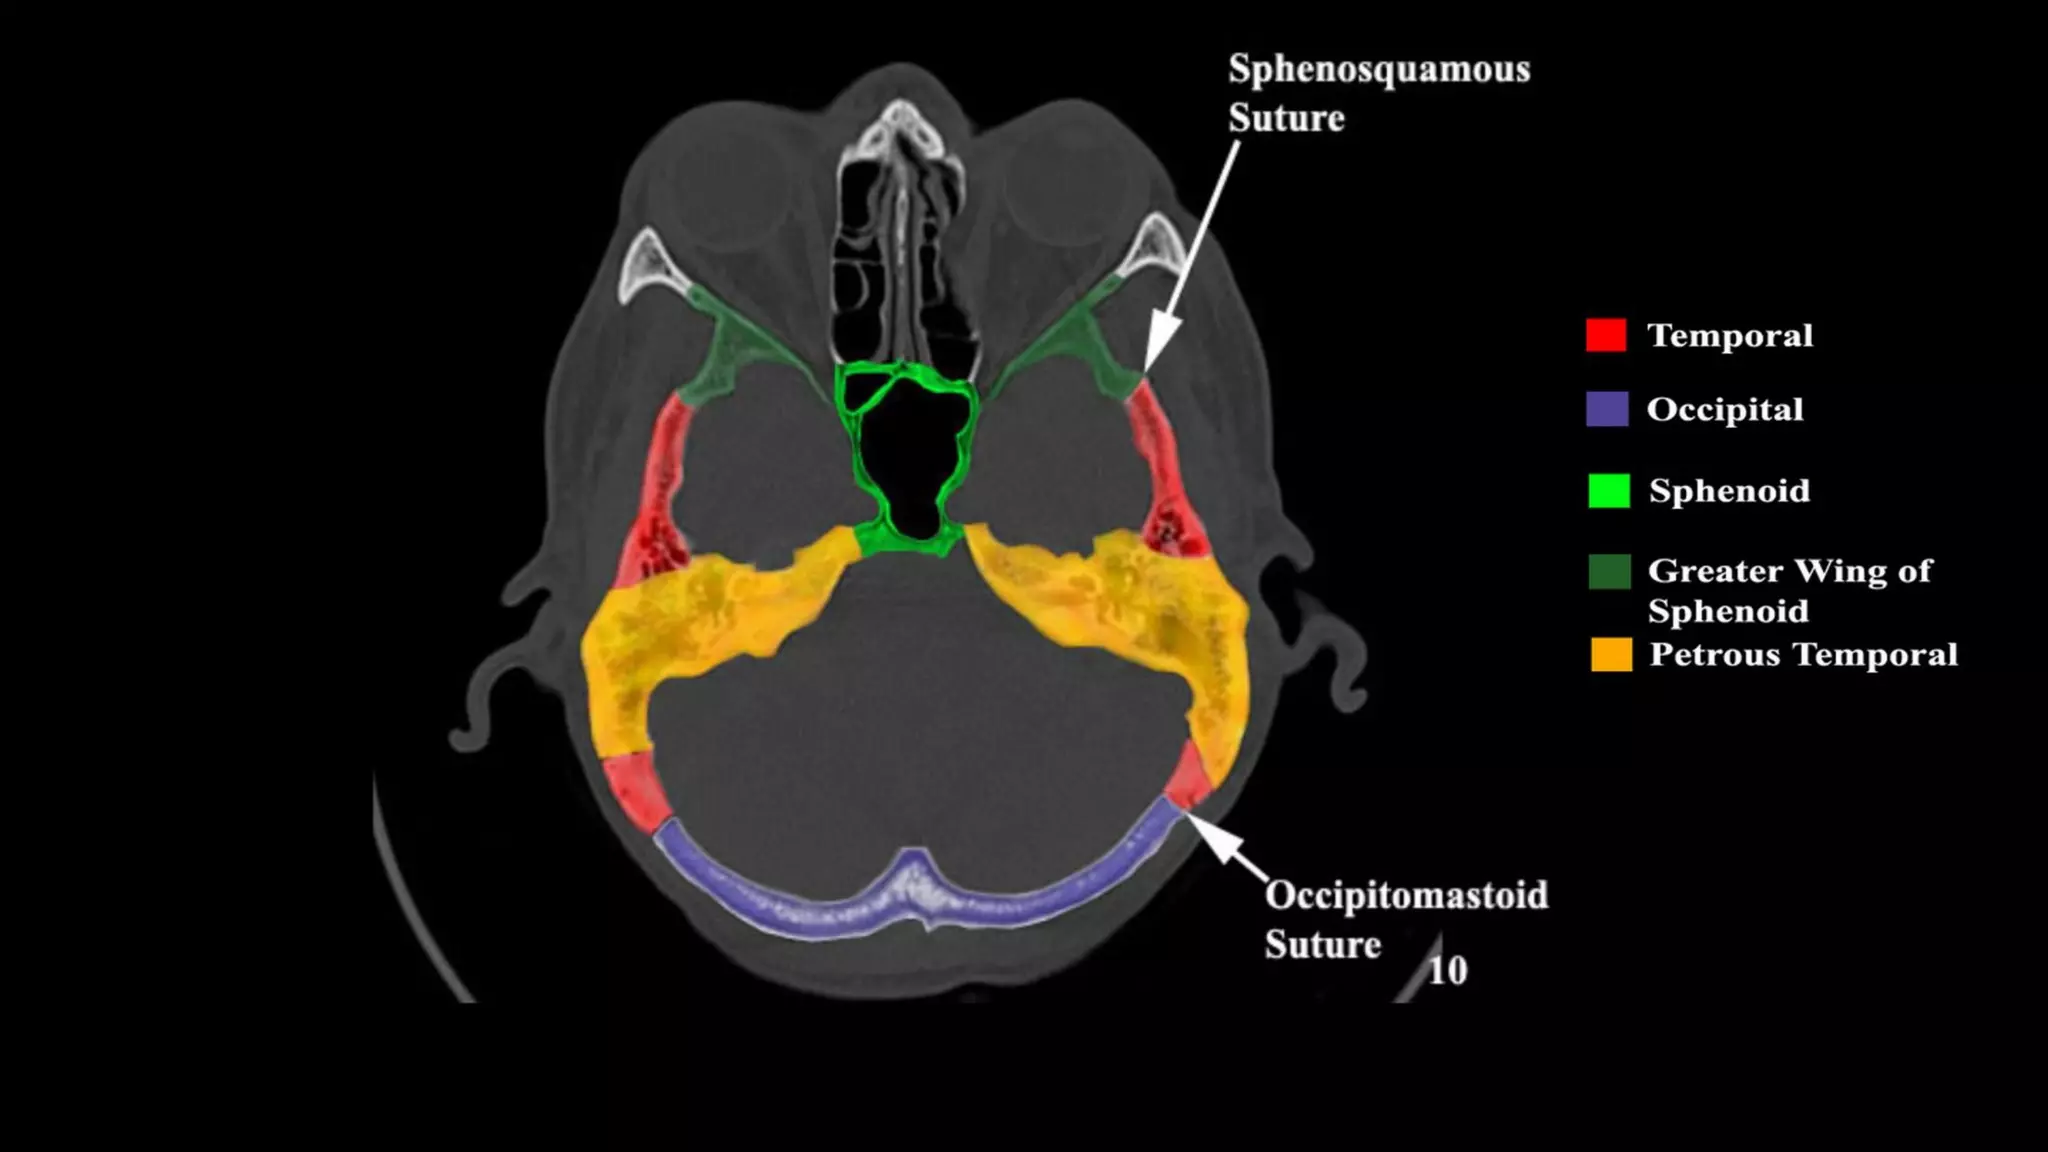

Pseudo-fractures

Extrinsic Fissures &

Sutures